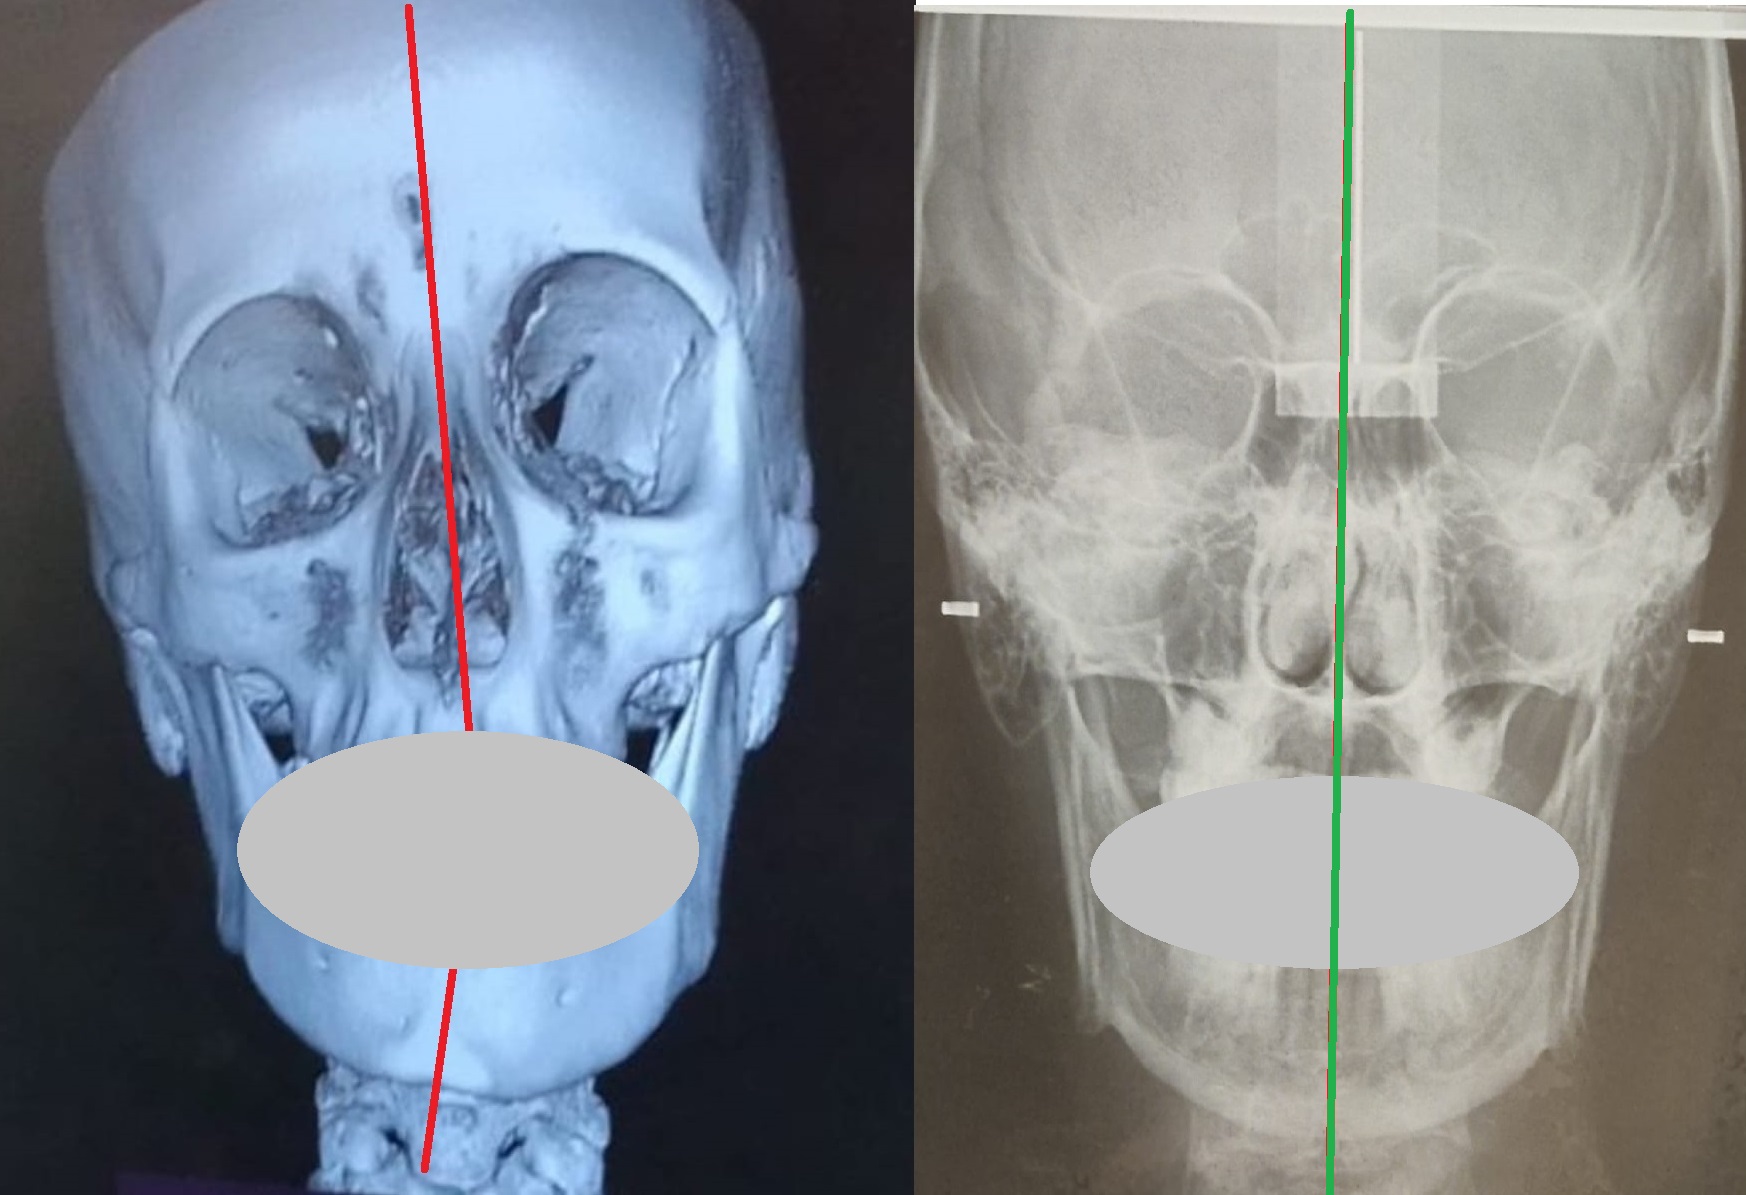

Non prendiamo come riferimento l’immagine di profilo più copiata nel mondo della postura e di certe discipline mediche come l’odontoiatria, la gnatologia e l’osteopatia; prendiamo l’immagine della scoperta OcclusioneGravità® che indica un teschio con rapporto scheletrico a-simmetrico:

Questa è la vista frontale.

Esistono anche lastre rx per farvi capire che non siete dei disegnini ma è realtà.

Per ragioni di praticità dobbiamo utilizzare un rapporto scheletrico molto evidente come questo:

Il rapporto scheletrico è molto simile all’immagine creata da Formia Maurizio e pubblicata nel suo libro nel 2009, copiata senza citarla in numerosi documenti e riviste scientifiche.

Abbiamo coperto volutamente e provocatoriamente i denti perchè lo scheletro si vede ugualmente non simmetrico anche senza bocca e denti. Si vede anche senza una lastra:

A livello di rx possiamo dire che cranio e mandibola, prima e dopo, sono diventati simmetrici applicando la scoperta del Meccanismo OG.

I condili della mandibola si riallineano, si riallineano le ossa SUI TRE PIANI SPAZIALI ruotando tra loro e inclinandosi fino ad arrivare ad una posizione di simmetria e di EQUILIBRIO MECCANICO ABITUALE.

Per la rx a destra abbiamo ricevuto complimenti anche da una prestigiosa università italiana che è tra le più prestigiose del mondo.

Il grande paradosso che vogliamo farvi comprendere che nessuna disciplina, università, centro di ricerca ha voluto approfondire (e comprendere) è che tolte le rx, tolta la “visione” medica del problema che non sta a noi approfondire, non siamo medici e non vogliamo esserlo, è che queste teste pesano dai 5 ai 7 KG e se inclinate di qualche grado a causa del Dis-Equilibrio tendono a cadere come una palla (freccia rossa evidenziata anche nelle immagini precedenti) e possono arrivare a pesare, ai nostri muscoli, anche 25 KG.